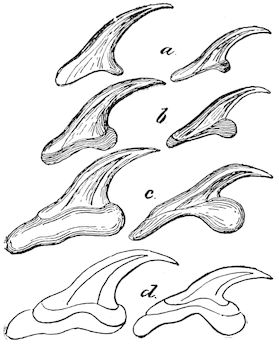

Fig. 9.—C, horn; P, modified skin forming the keratogenous membrane; O, horn core, exhibiting a double sinus.

(2.) The horn-secreting membrane is formed by the skin, which undergoes special development around the base of the horn and comes to resemble that of the coronary band, from which the hoof or claw is secreted. The band is about one-fifth of an inch in breadth. The papillæ of the dermis are specially developed at this point, and the epithelium which they secrete eventually forms the horn.

The internal surface of the growing horn is adherent to the horn core through the medium of another tissue formed by a specially differentiated periosteum which is continuous with the periosteum covering the frontal bone. It is not a true periosteum, but a vascular tissue formed of papillary layers analogous to those of the podophyllous tissue of the ox’s claw or horse’s hoof.

This keratogenous membrane receives a rich vascular supply from the arterial circle formed at the base of the horn core by a division of the external carotid, the blood conveyed by which is freely distributed to the enlarged papillæ. The great vascularity of these parts 23explains why lesions of the horns are often followed by such profuse bleeding.

(3.) The horn secreted by the papillæ of the horn band (which is analogous to that of the coronary band of the horse) forms a cone varying in its curve in various breeds. Its base is hollow, and contains little depressions holding the papillæ from which the horn is secreted. From its base up to the end of the horn core the walls progressively increase in thickness. From this point it is solid; in a fully-grown horn the bone does not extend more than one-half or two-thirds of the entire length.

Fig. 10.—Dressing for fracture of the horn.